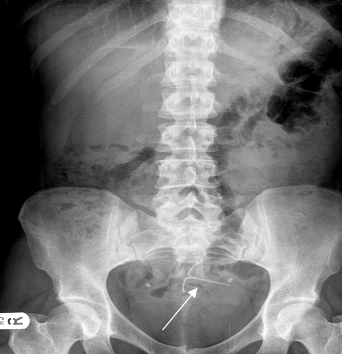

A Louisiana woman’s Mirena injury lawsuit has survived a motion to dismiss by Bayer Pharmaceuticals. A federal judge ruled on September 23 that new information set forth in Latoya Thompson’s affidavit create an issue of fact over whether her Louisiana Product Liability claims were filed... Read More